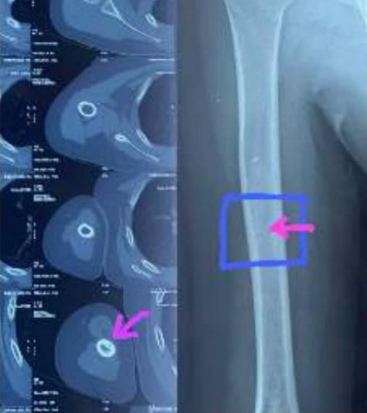

SRM Global Hospitals Treats 7-Year-Old Boy from Jharkhand for Rare Bone Tumor

Osteoid osteoma ranks as the third most common benign bone tumor in children, with an occurrence rate of 1 in 1,00,000. The surgery was challenging due to the tumor’s tiny size, measuring just 5 mm x 5 mm, and its location deep within the shaft of the boy’s upper arm bone. Chennai, 3 December 2024: […]